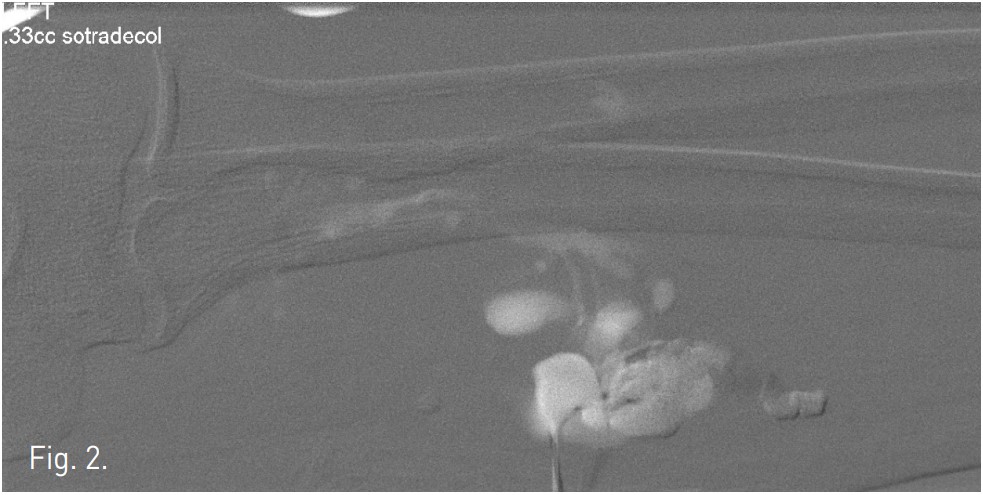

Venography demonstrates dilated, tortuous veins along the medial aspect of the proximal forearm draining into normal veins (Fig. 1). Negative digital subtraction angiography shows filling-defects from displaced contrast material in the vascular malformation during sodium tetradecyl sulfate foam injection (Fig. 2). A native image of the forearm demonstrates stasis of contrast material within the venous malformation after foam sclerotherapy (Fig. 3). T2 STIR imaging shows a 10.3 x 2.5 x 2.3 cm high signal intensity mass centered within the flexor digitorum superficialis consistent with slow-flow vascular malformation. The high signal represents the extent of the vascular malformation as well as post-treatment edema or inflammation (Fig. 4). Post-contra st T1 imaging with fat suppression demonstrates heterogeneous enhancement of the mass with notable areas of low signal representing the areas of thrombosis/sclerosis. The residual irregular enhancement represents postprocedural inflammation. Of note, there are no enhancing serpiginous structures (Fig. 5).

Fig. 2.

Fig. 2. Negative digital subtraction angiography shows filling-defects from displaced contrast material in the vascular malformation during sodium tetradecyl sulfate foam injection.